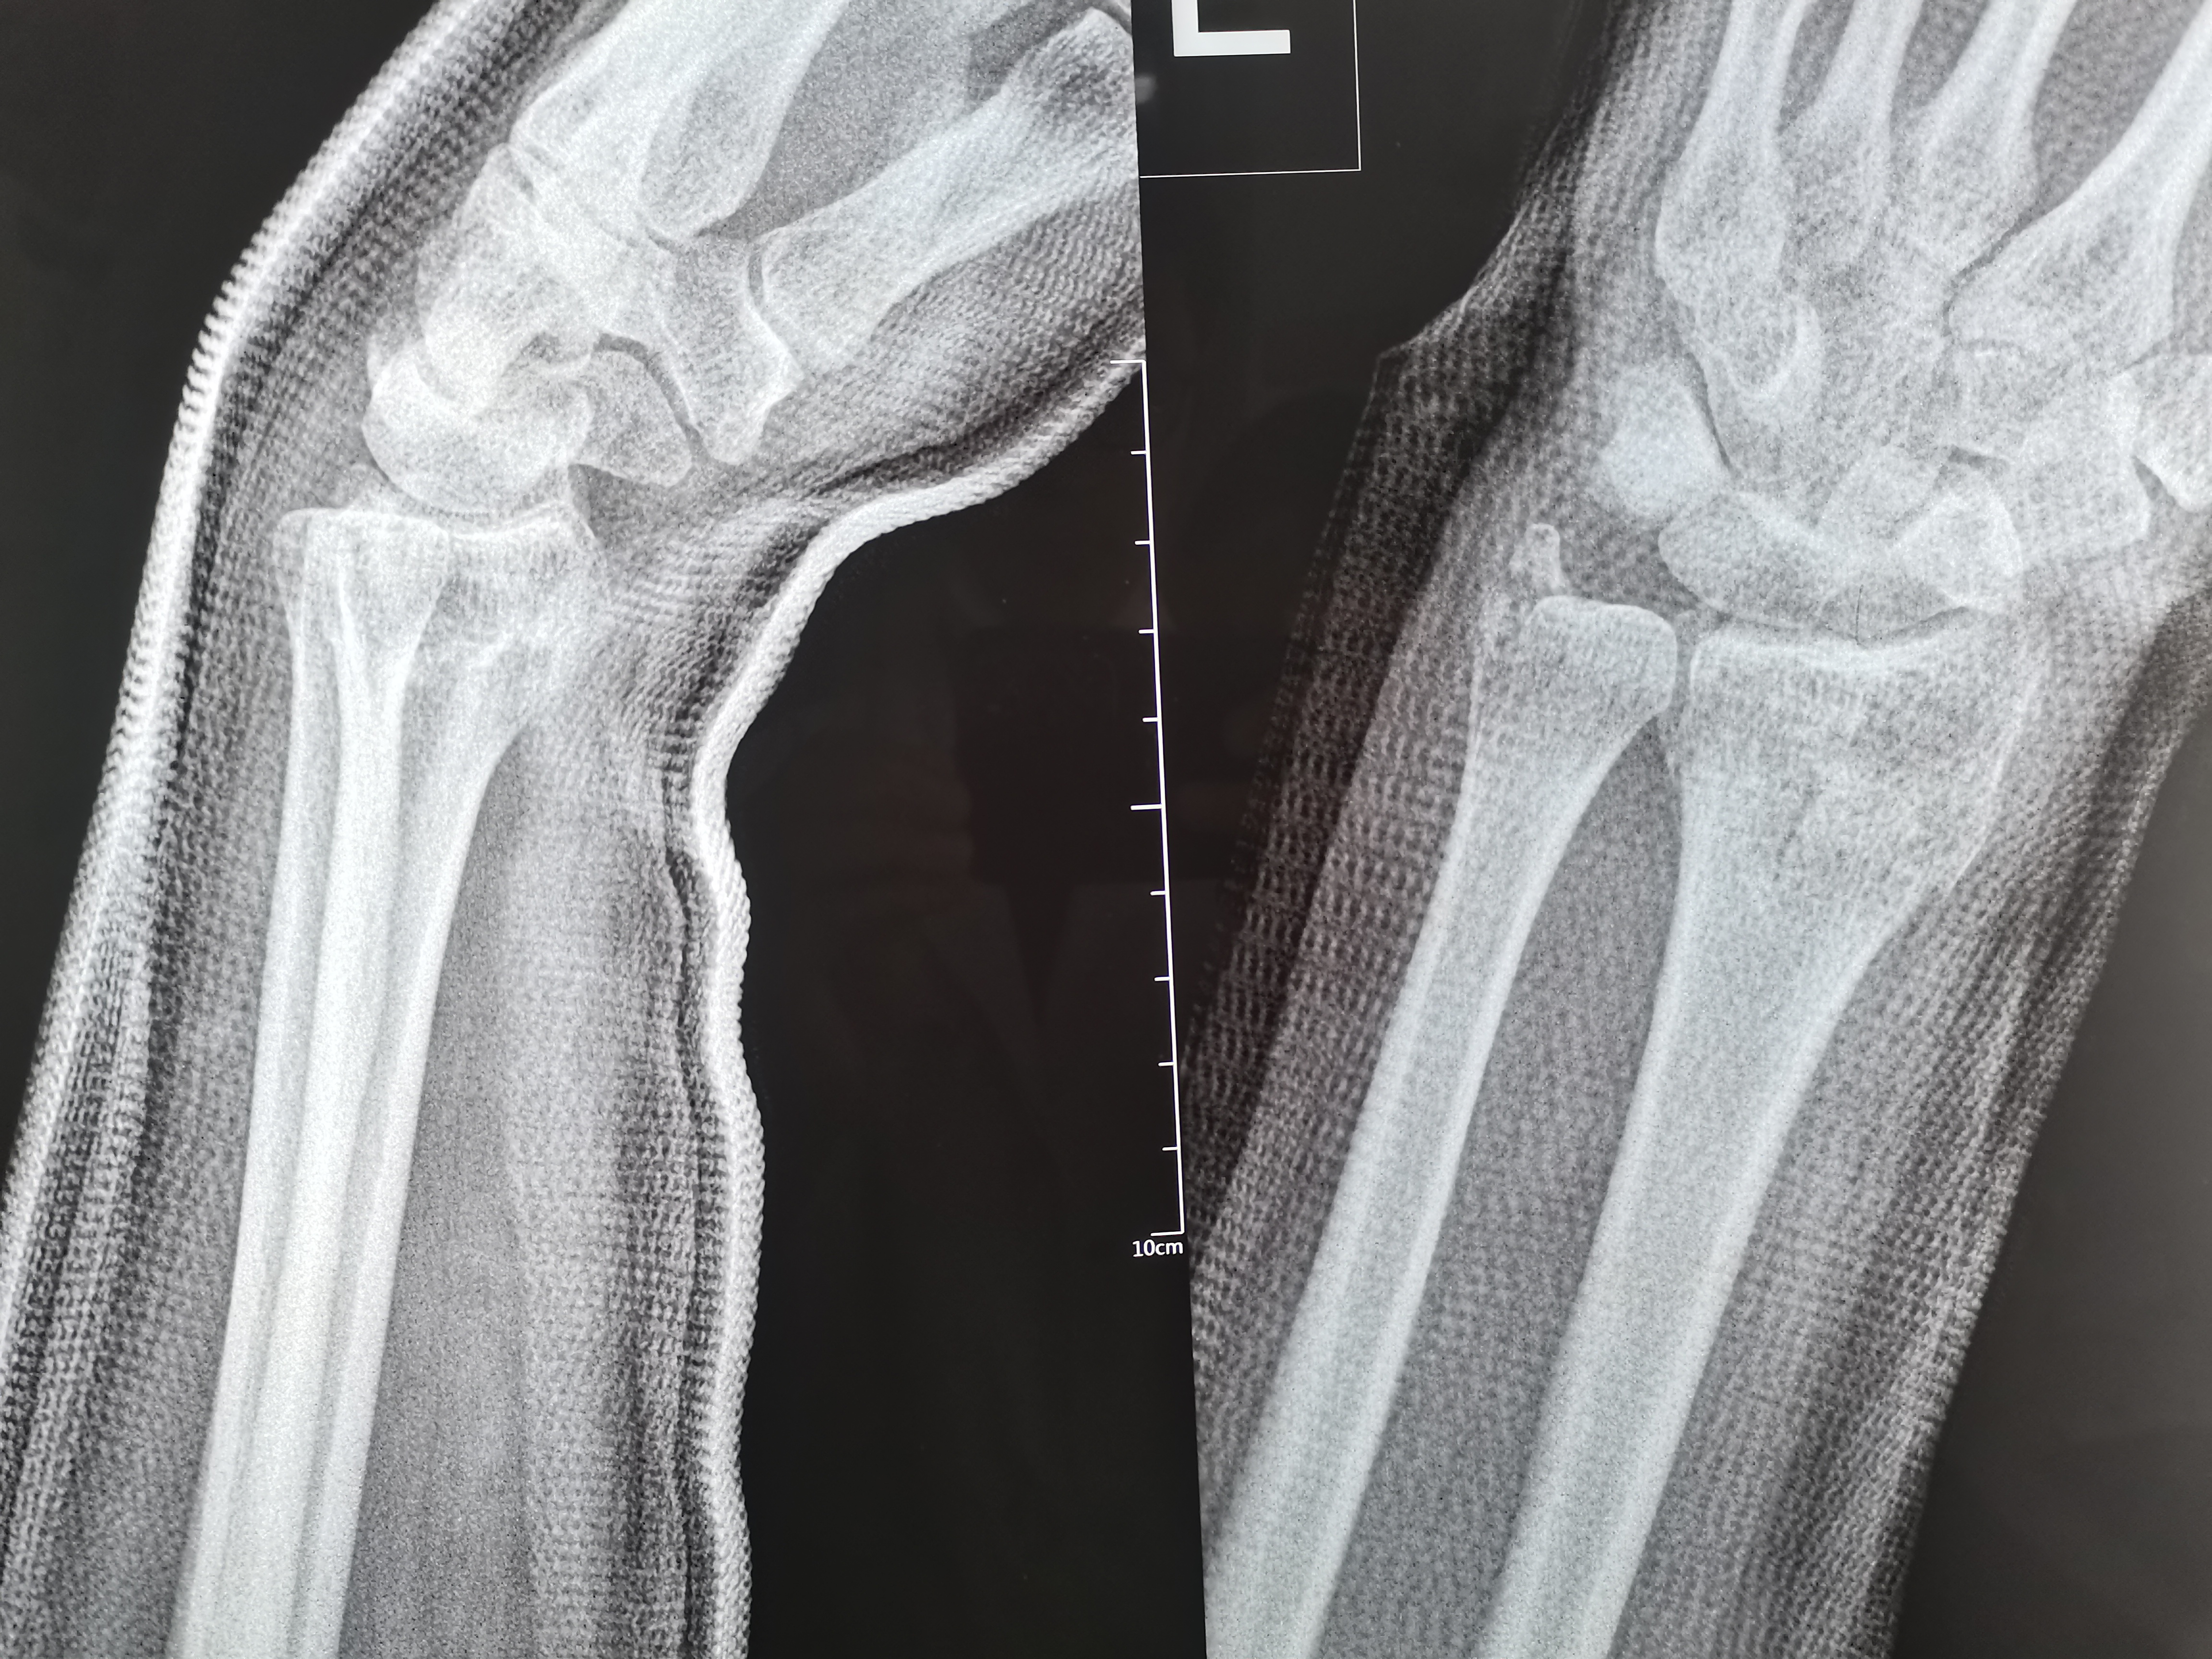

1. 评估病情:通过X线片明确骨折类型(如Colles骨折、Smith骨折、Barton骨折)、移位方向(掌侧/背侧移位、桡侧偏移、短缩等),同时检查腕部神经(正中神经为主)、血管功能。

以常见的Colles骨折(背侧移位)为例,复位步骤如下:

3. 调整掌倾角与尺偏角:通过微调牵引力方向,使桡骨远端掌倾角恢复至10°-15°,尺偏角恢复至20°-25°,此时可触及骨折端稳定的骨擦音。

1. 影像学检查:复位后即刻复查X线片,确认骨折对位对线良好,若仍有移位需再次复位。

手法复位的成功与否取决于对骨折移位规律的掌握和操作技巧的熟练度,复位后定期复查X线片(复位后即刻、1周、2周、4周)至关重要。多数患者通过规范的手法复位和后续康复,可恢复良好的腕关节功能。